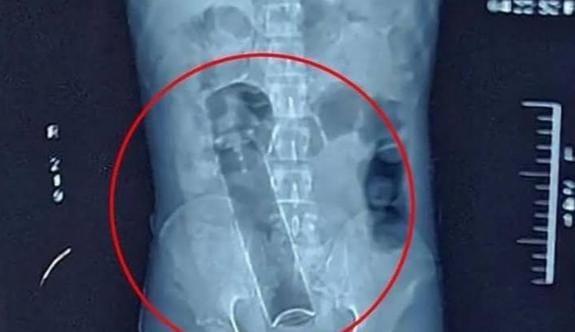

Um homem de 42 anos deu entrada no hospital de Trauma de Campina Grande com um desodorante inserido no ânus.

De acordo com informações obtidas pelo ClickPB, após ser atendido na triagem do hospital a equipe médica realizou um exame de imagem antes de tentar retirar o objeto.